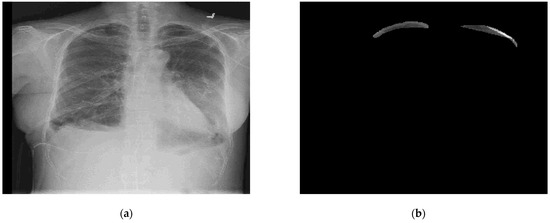

6.1. Results for Segmentation of Pneumothorax